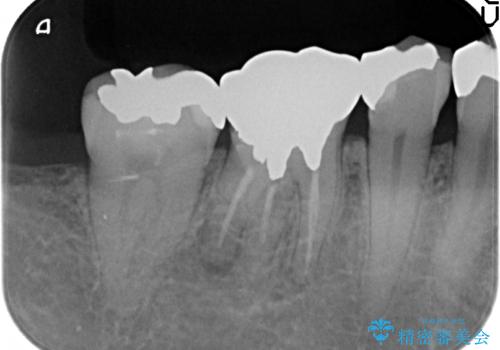

- 他院にて根尖病変があるため根管治療を勧められ当院にいらっしゃった方の症例です。

再根管治療を行い病変の縮小傾向を確認後、オールセラミッククラウンによる補綴を行いました。